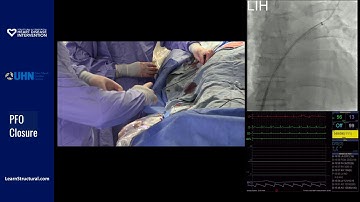

PFO Device Preparation